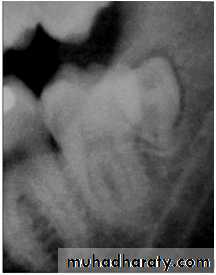

Paramolar blocking the eruption of 3rd molar.

most often affects the mandibular 3rd molars &maxillary canines.

CAUSES: due to obstruction from crowding.

occasionally, may be due to an abnormal eruption

path, presumably because of unusual orientation of

tooth germ.